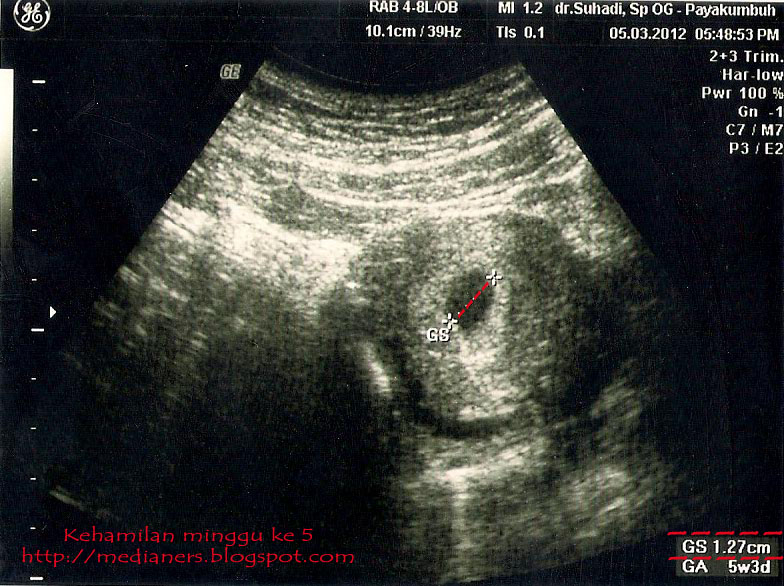

Hasil usg 4d bayi umur 8 bulan ( jenis kelamin perempuan ). Moms, begini caranya membaca hasil usg : Nah, tapi ada juga nih yang masih bingung. Gambar bayi yang bisa anda lihat juga tergantung dari sudut tembakan dari transduser usg atau alat yang dipakai untuk mengambil gambar usg. Biasanya parents akan ditunjukkan gambar hasil pemindaian rahim pada layar oleh dokter dan diberikan foto hasil cetaknya. Cara membaca gambar hasil usg bayi untuk jenis kelamin ada sejumlah faktor penentu yang membantu calon orang tua mengetahui jenis kelamin janin melalui gambar usg. Contohnya seperti yang dilakukan wanita asal swedia yang merupakan calon ibu dari 2 bayi kembar ini. Oleh karenanya, tingkat kesalahan identifikasi janin perempuan lebih besar daripada janin laki2. Bahkan pada janin yang lebih besar bisa tampak buah zakar yang berada dalam kantung zakar. Melalui hasil usg, dokter dan ibu hamil dapat mengetahui kondisi janin dalam kandungan. Usg umur 6 bulan,usg umur 7 bulan, hasil usg janin umur 8 bulan Janin yang terlihat tersebut masih berupa titik janin saat usia kehamilan masih 5 minggu. Walaupun ukurannya masih kecil sekali tetapi janin sudah bisa terlihat dalam pemeriksaan usg.

Hasilnya, akan terlihat jaringan, organ, dan juga anatomi dari janin. Umumnya tidak ada perbedaan yang terlalu banyak antara cara membaca hasil usg 2d dan 3d. Faktanya, tes ini menggunakan jenis gelombang ultrasonik yang sama dengan yang digunakan untuk memantau perkembangan janin. Melalui hasil usg, dokter dan ibu hamil dapat mengetahui kondisi janin dalam kandungan. Seperti pemindaian 3 dimensi dan 4 dimensi, rentang waktu yang disarankan adalah kehamilan 24 hingga 32 minggu. Hasil usg kehamilan 5 minggu yang normal. Di lembaran hasil usg, akan tertera gambar dan susunan huruf serta angka yang rapi, yang menunjukkan keterangan tentang perkembangan janin. Kebanyakan janin perempuan akan memiliki detak jantung sekitar 140 per menitnya. Usg ini menunjukkan hasil yang lebih jelas, seperti warna kulit melalui pencahayaan. Hasil usg 4d bayi umur 8 bulan ( jenis kelamin perempuan ). Melihat jenis kelamin calon bayi nah, ini dia yang biasanya ditunggu mampaps ketika akan melakukan pemeriksaan usg. Sementara gambar 10c adalah gambar janin perempuan yang paling mirip dengan kelompok perempuan. Janin perempuan diidentifikasi dari gambaran 2 buah bibir kemaluan.

Cara membaca gambar hasil usg bayi untuk jenis kelamin ada sejumlah faktor penentu yang membantu calon orang tua mengetahui jenis kelamin janin melalui gambar usg. Melalui hasil usg, dokter dan ibu hamil dapat mengetahui kondisi janin dalam kandungan. Walaupun begitu tetap ada hasil usg yang memenuhi syarat yang bisa dibaca bahkan oleh orang awam, misalnya saat ada gambar yang jelas menunjukkan panjang janin di trimester 1, irama dan frekuensi jantung. Usg jenis kelamin janin usia 5 bulan dengan 4d maupun 2d sudah kelihatan. Kebanyakan janin perempuan akan memiliki detak jantung sekitar 140 per menitnya. Oleh karenanya, tingkat kesalahan identifikasi janin perempuan lebih besar daripada janin laki2. Walaupun ukurannya masih kecil sekali tetapi janin sudah bisa terlihat dalam pemeriksaan usg. Saking bingungnya sampai tanya pendapat. Cara membaca hasil usg 3d. Di lembaran hasil usg, akan tertera gambar dan susunan huruf serta angka yang rapi, yang menunjukkan keterangan tentang perkembangan janin. Hasil gambar usg bayi perempuan. Yang perlu anda tahu saat membaca hasil usg. Melihat jenis kelamin calon bayi nah, ini dia yang biasanya ditunggu mampaps ketika akan melakukan pemeriksaan usg.